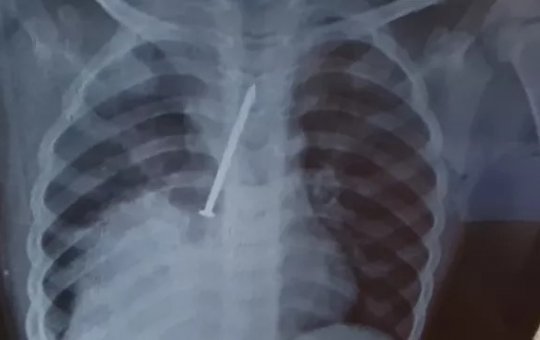

Cremeb-Ba fará apuração de atendimento de garoto que morreu com prego no pulmão

Cauan Araújo Conceição, de 3 anos, morreu após ficar com objeto no pulmão